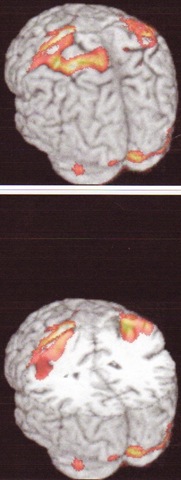

PC_Has_A_Brain_Shock_0001 PC_Has_A_Brain_Shock_0002I've heard suggestions that I haven't got a brain, and if I did I've never used it.  I know, I've heard you.  But me baby, I've got statistics, I've got facts.  I've got pictures.

Herewith the shocking evidence: actual picture proof that I both have a brain and, from those few splodges of colour there, that I sometimes even use it.  Frightening, isn't it.

(The pics, by the way, come from a scan done as part of a stroke study, for which the researchers needed some normal brains.  I did warn them about the inherent risk in using mine, but you just can't tell some people anything.  I've learned that.)